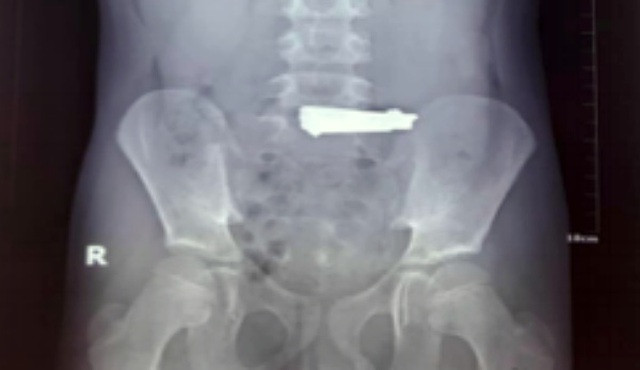

Trung Tâm Y Tế huyện Cẩm Khê (Phú Thọ) tiếp nhận cấp cứu một trẻ trai 9 tuổi, có biểu hiện ho nhiều, đau bụng. Qua thăm khám và nội soi dạ dày, các bác sĩ phát hiện chiếc bấm móng tay có kích thước 6x1,6 cm, nằm tại vị trí phình vị lẫn thức ăn, gây tổn thương xước niêm mạc dạ dày. Ngay lập tức, bệnh nhi được nội soi gắp dị vật thành công.

Cậu bé cho biết học theo các video trên youtube nên đã nuốt bấm móng tay vào bụng.